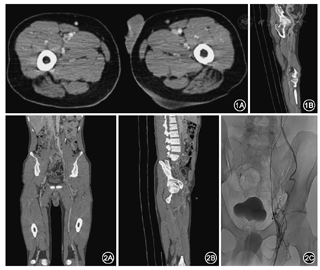

本研究中60例患者共780支血管接受CTV检查,326支血管有阳性发现(41.8%,326/780)。患者CTV征象主要为扩大的静脉管腔内局灶或多发中心性、偏心性或不规则充盈缺损,或呈条带状累及一支或多支血管,周围侧支循环形成。由于静脉回流受阻,患肢肌肉及皮下脂肪组织明显肿胀,故可见水肿增厚筋膜影(图1,图2)。

60例患者共420支血管行单侧下肢静脉DSA诊疗,332支血管有阳性发现(79.0%,332/420)。患者DSA征象主要为单发或多发充盈缺损,部分血管管腔不显影,周围侧支循环形成。下肢静脉形成血栓的患者通过抬高患肢,增加对比剂总量增加下腔静脉显影度,小腿部还可加袖带,注射对比剂时触发测压,增加小腿压迫从而增加下腔静脉血流回流量。血栓分布情况及诊断结果对比分析分别见表1,表2。以DSA检查结果为金标准,低剂量CTV的灵敏度、特异度分别为96.2%、92.6%。低剂量CTV和DSA两种方法检查结果在kappa一致性检验中kappa值为0.860,P<0.05,说明两种方法对DVT诊断具有很好的一致性;在配对χ2检验,P=0.263,两种检查方法差异无统计学意义。患者辐射剂量均值(225±44) mGy·cm。均显示低剂量CT下肢静脉造影对DVT的诊断有很高的准确性(图3)。